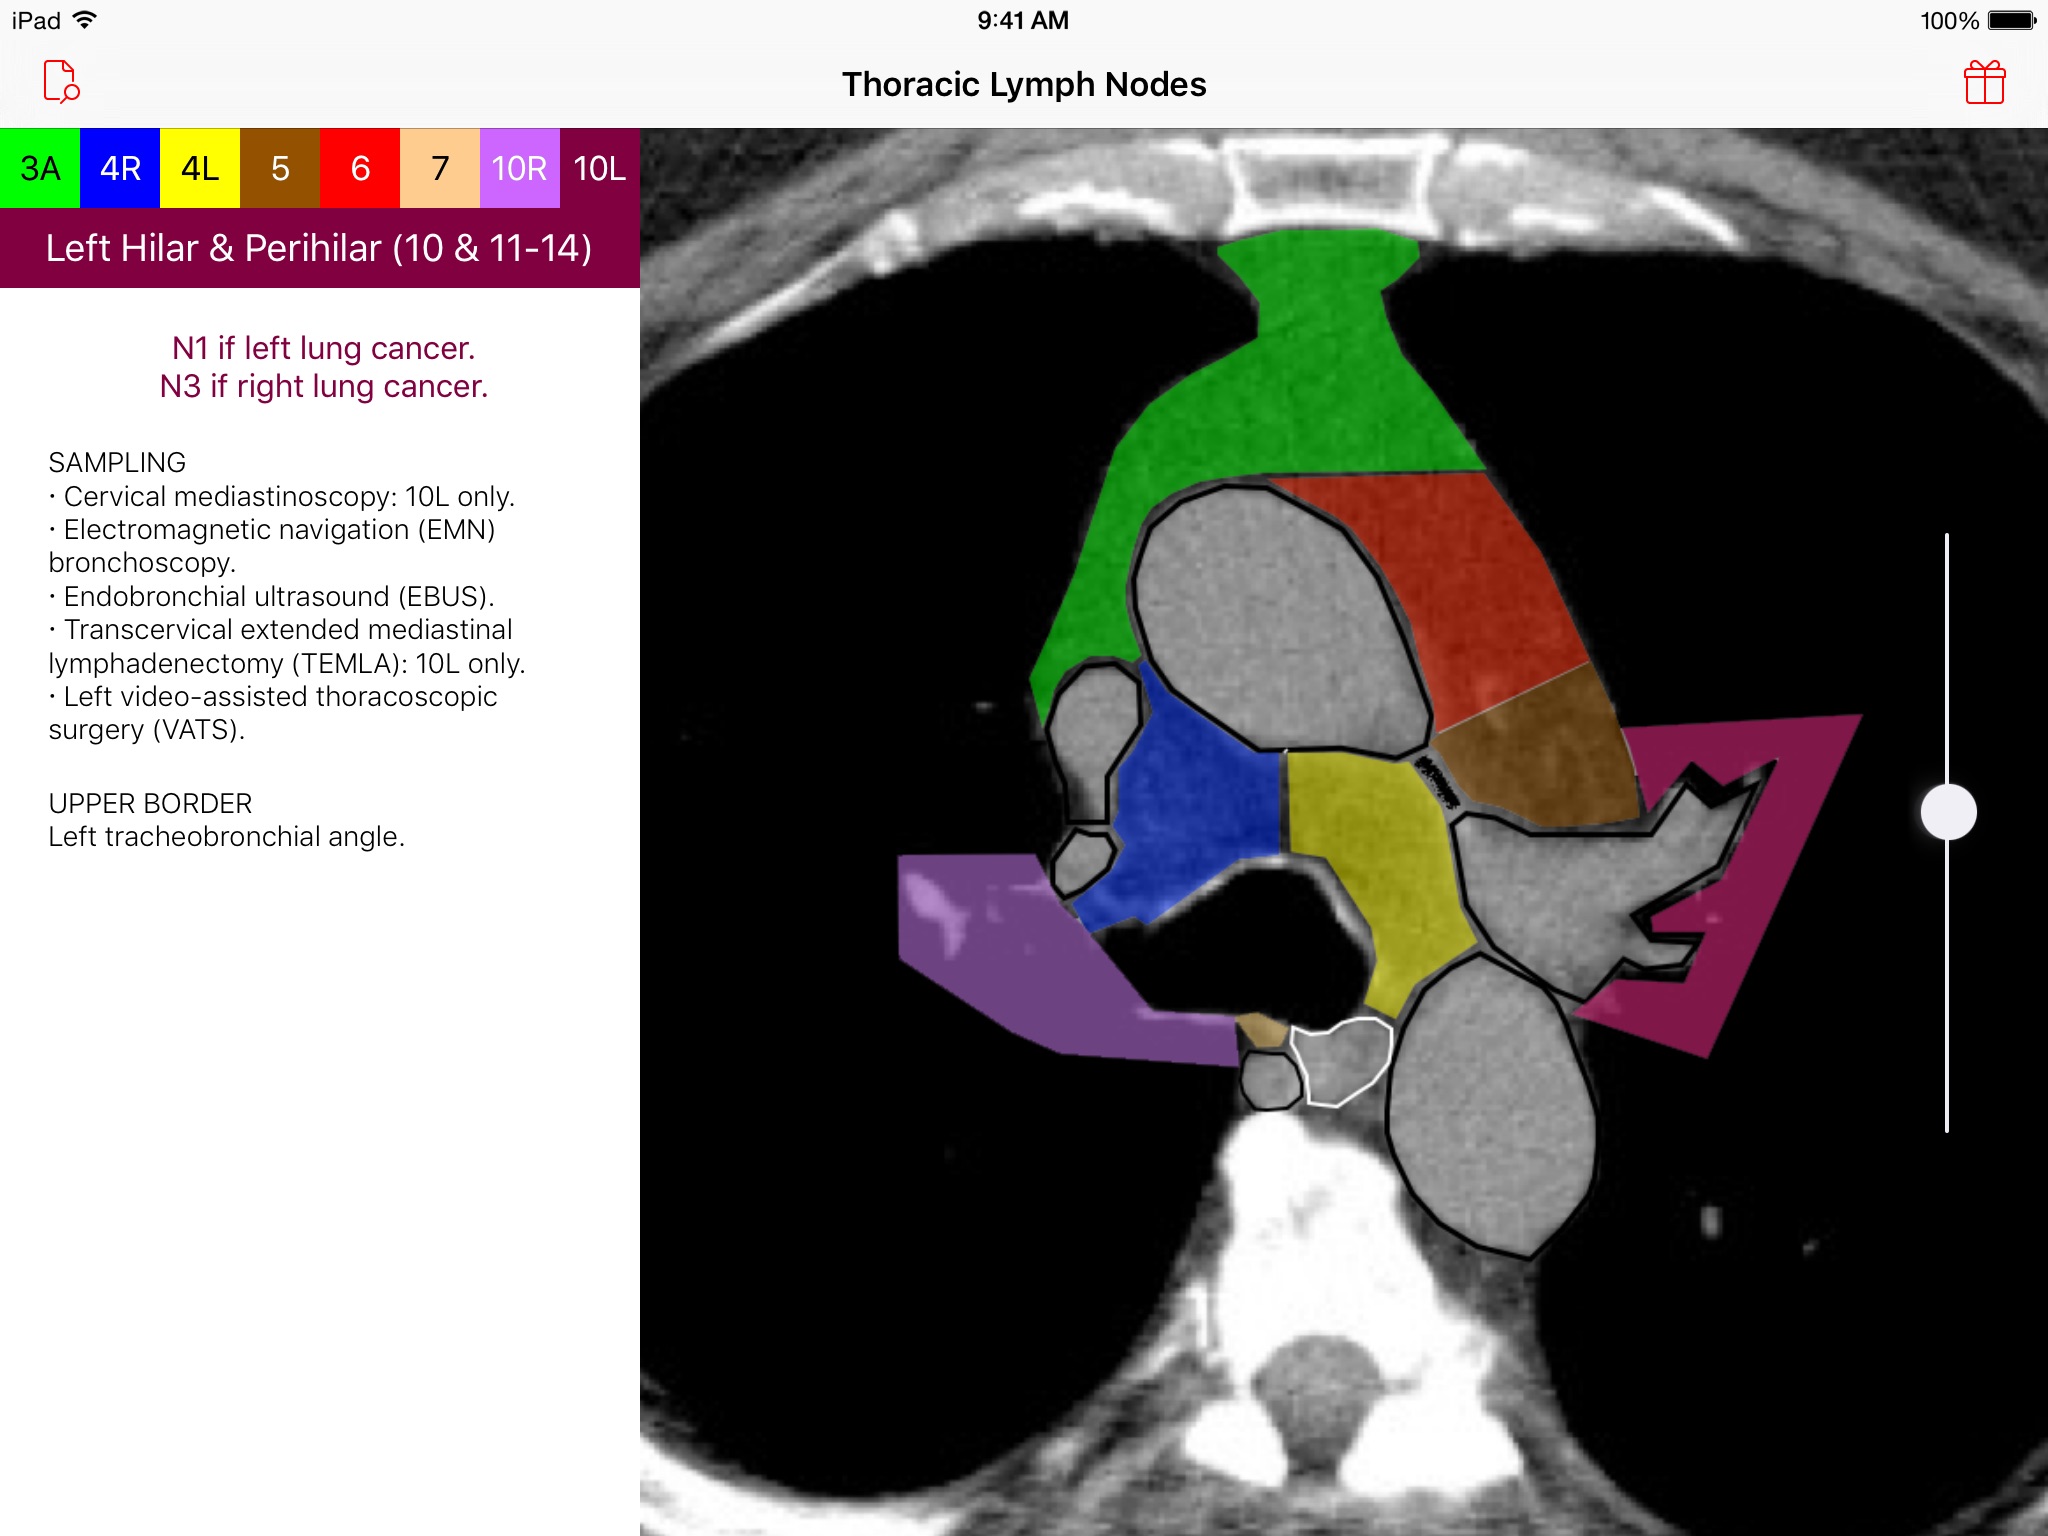

Introducing the Thoracic Lymph Node Map app, an elegant tool that provides healthcare professionals with a color-coded CT lymph node map adapted from the International Association for the Study of Lung Cancer (IASLC) lung cancer project. Effortlessly navigate through CT images of the chest and view beautifully illustrated, color-coded thoracic CT lymph node map anatomic definitions for each lymph node station. Delve deeper and learn more about classification, sampling options, and anatomic details of each lymph node station. Browse · Regional thoracic lymph node station territories · Relationships between different regional lymph node stations within the chest Discover · Clinical regional lymph node classification for each lymph node station · Sampling options for each lymph node station · Anatomic boundaries for each lymph node station Requirements · A device with iOS 8 or later This app was developed as a service to the medical community and is provided free of charge and free of advertising.